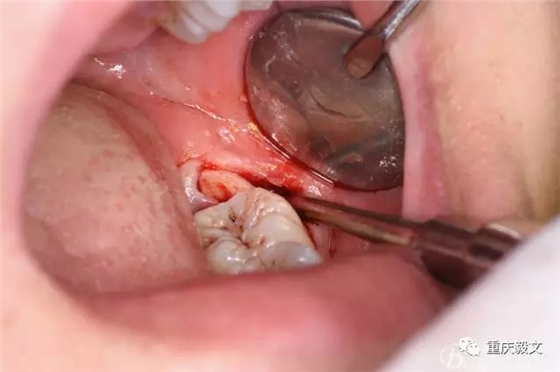

圖6.分離頰側(cè)牙齦,目的使牙冠和牙根能順利從牙齦軟組織脫位。

圖7.高速渦輪鉆分牙

圖8.先從頸部橫斷38